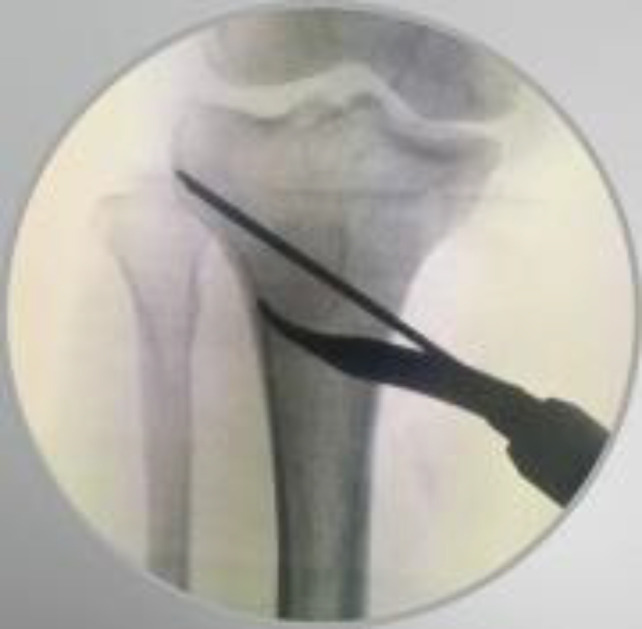

Medial open-wedge high tibial osteotomy (MOWHTO) is increasingly recognized as the preferred treatment option for active patients with varus malalignment and medial compartment osteoarthritis of the knee. This procedure aims to delay the degenerative process while alleviating pain and dysfunction. In this technical note, we aim to describe the tips and tricks for performing a safe MOWHTO, drawing on recent literature.